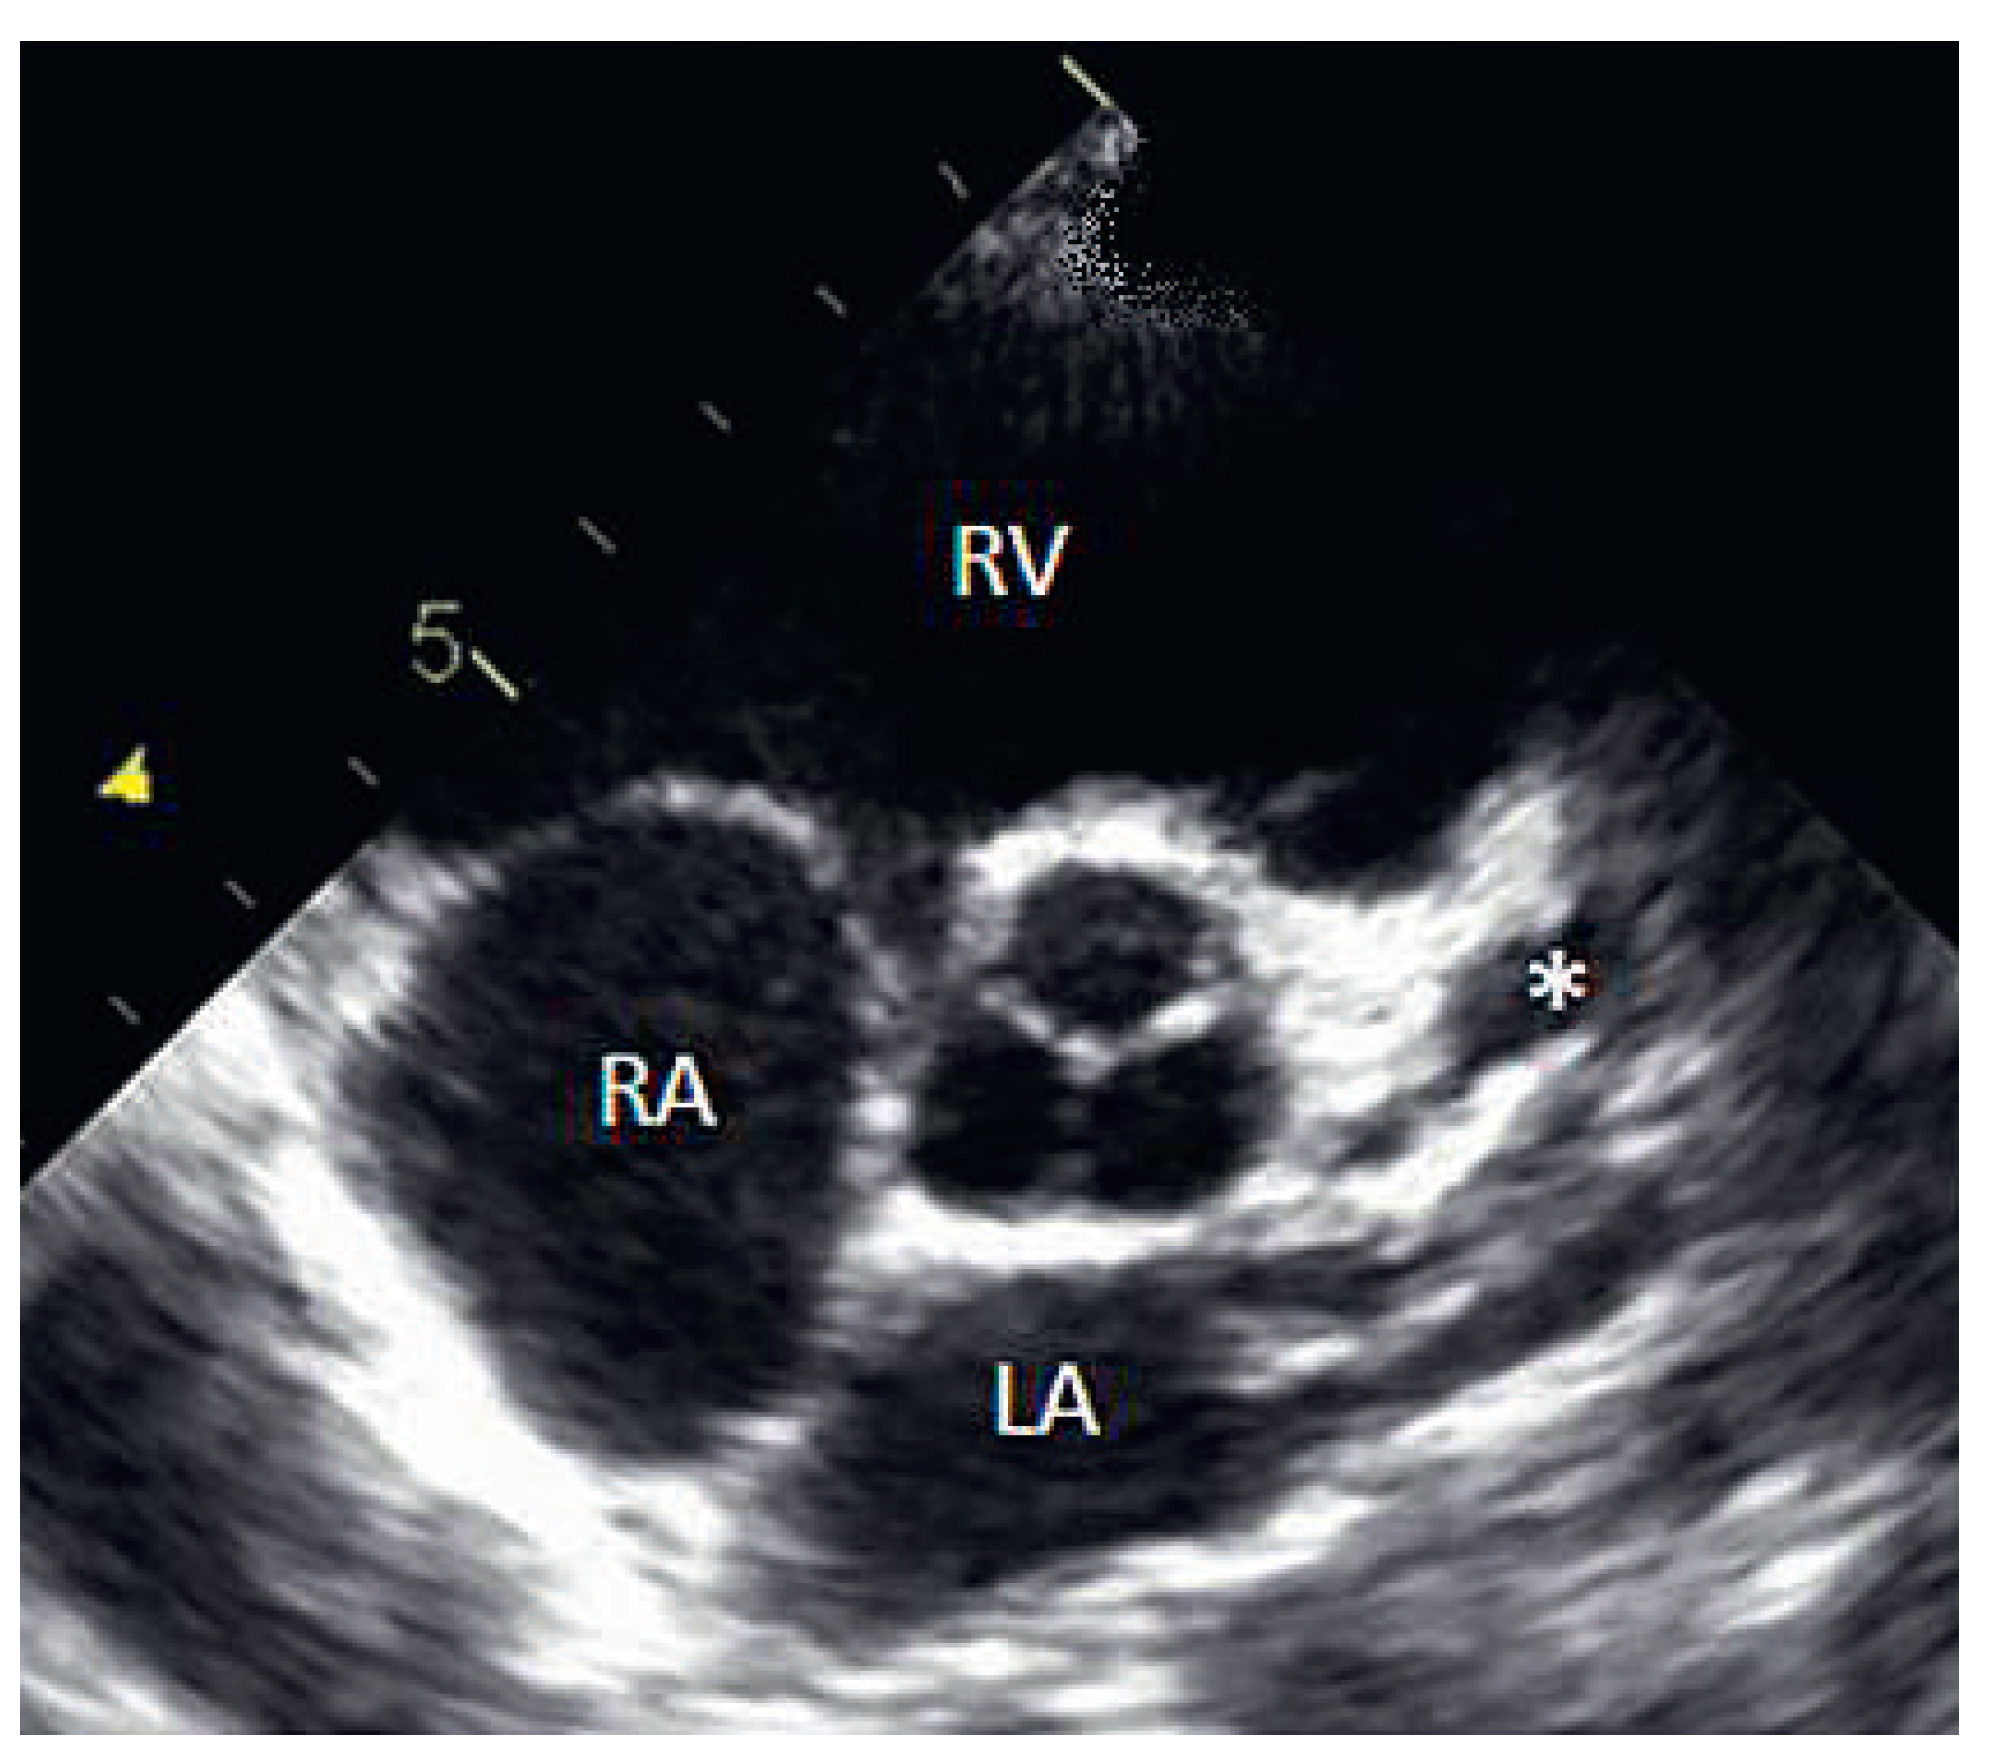

On the tenth day, we performed transthoracic echocardiography (Figure 1 and Figure 2), which revealed normal biventricular size and function, without hypokinesia. There was no pericardial effusion, no valvular disease, but a proximal enlargement of the left anterior descending coronary artery (LAD) was visualised. On the same day, because all these elements suggested Kawasaki disease (KD), treatment with intravenous polyvalent immunoglobulin (IVIG 2 g/kg as a single infusion: Privigen 70 g) and high-dose aspirin (80 to 100 mg/kg/d: 750 mg four times a day for eight days) was started, with rapid resolution of symptoms and apyrexia within 24 hours. Cardiac computed tomography (CT; Figure 3) showed three-vessel aneurysmal coronary artery disease (CAD) including a giant aneurysm of the proximal LAD (9 mm), an aneurysm of the circumflex artery (6 mm) and two aneurysms of the right coronary artery (4 and 5 mm). There was no vascular involvement in the cerebral and abdominal magnetic resonance imaging (MRI).

Figure 2.

2D echocardiography (* = LAD aneurysm, + = right coronary artery aneurysm).